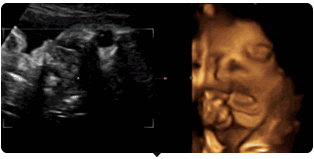

你可以通过美国GE-730高清四维彩超

看到胎宝宝最可爱撩人的画面——

麻麻,我在挠耳朵